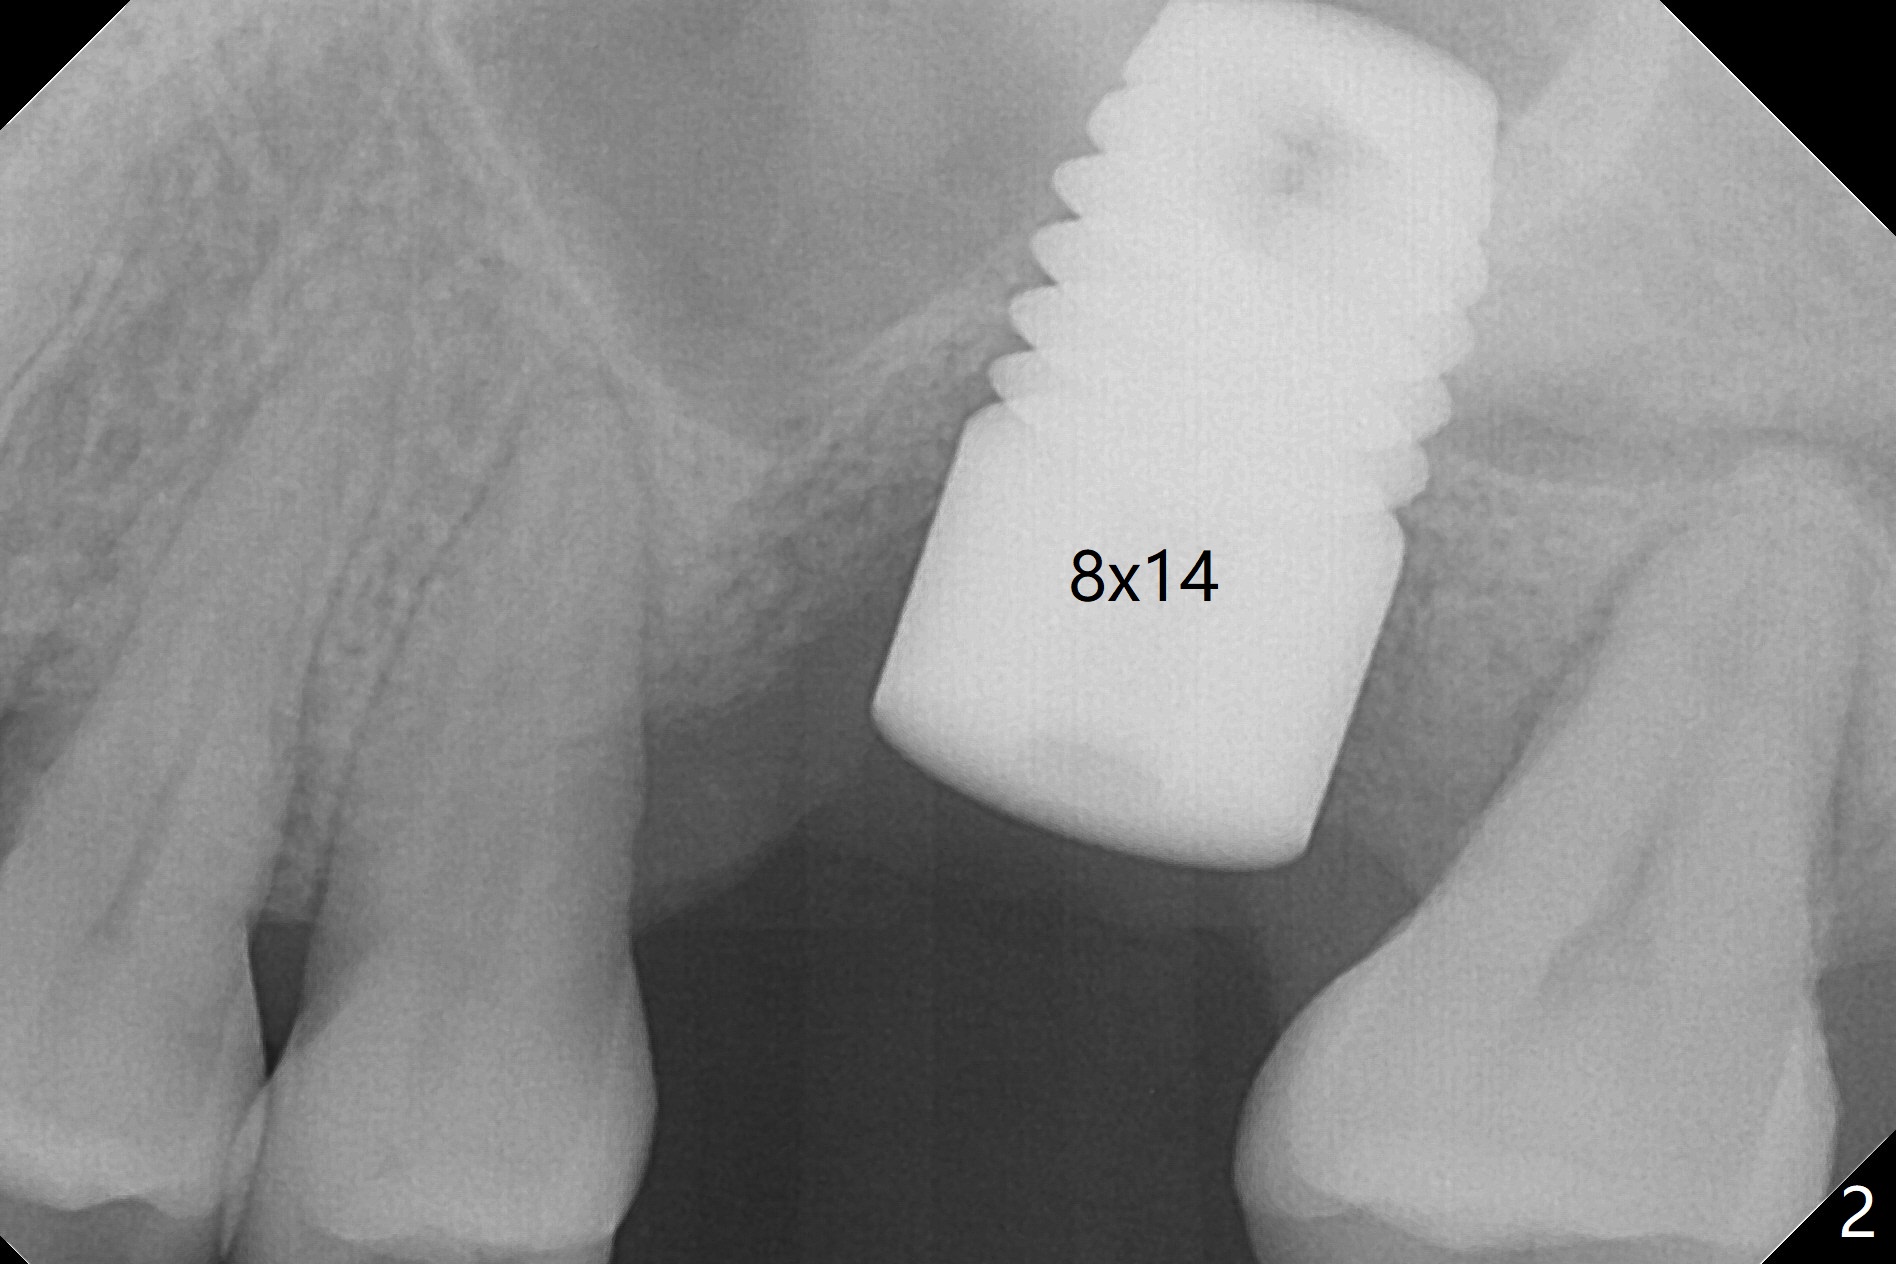

Three months post cementation, the implant at #14 is found loose (Fig.1: 6.5x11 mm) and removed. After removal of minimal granulation tissue, normal saline disappears into the apical end of osteotomy. In fact there is no bone apically, although the sinus membrane is intact. After try in of various taps (tapered and cylindrical, bone- and tissue-level), a 8x14 mm dummy implant is placed (Fig.2), followed by Osteogen plug and the same sized definitive implant, which has to be placed deeper to obtain ~ 45 Ncm (Fig.3). There is minimal thread engagement. If the implant fails, place 2 layers of PRF membrane apically, bone graft and 1 layer of PRF coronally for ridge preservation. A healing abutment will be placed to expose the coronal end of the implant ~ 4 months postop. The tissue-level implant remains subgingival 4.5 months postop (Fig.4). A 8 mm healing cuff cannot be placed even after laser gingivectomy. The implant is 2 mm subcrestal mesially. Torque wrench cannot reverse the implant at 60 Ncm. The implant is later reversed with Tatum wrench until it is turned with the torque wrench at 30 Ncm. The implant remains stable, while the healing cuff with Triple Antibiotic Ointment is placed. The healing cuff is stable 2 weeks later (Fig.5 C). With progressive loading for a month, a crown is cemented 9 months postop. There appears no bone loss 2.5 months post cementation (11 months postop, Fig.6). Return to Upper Molar Immediate Implant, Armaments, IBS #3 Xin Wei, DDS, PhD, MS 1st edition 04/30/2018, last revision 04/14/2019